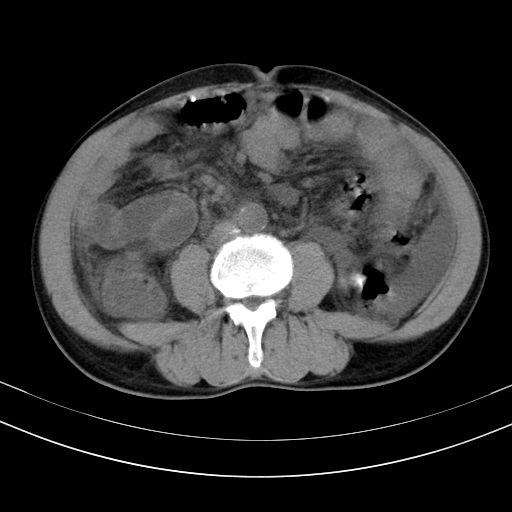

以下是引用随光逐影在2010-2-28 10:23:00的发言:[br]1)考虑肝癌;建议行ct增强扫描检查。2)肝硬化,脾大,腹水。3)慢性胆囊炎。

以下是引用dyqct在2010-2-28 16:44:00的发言:[br][quote]以下是引用随光逐影在2010-2-28 10:23:00的发言:[br]1)考虑肝癌;建议行ct增强扫描检查。2)肝硬化,脾大,腹水。3)慢性胆囊炎。